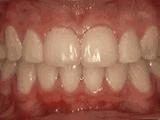

第二种

前牙移位,因为有牙齿缺失,导致相邻牙齿开始没有秩序的左右移动,经过矫正后是这样的~